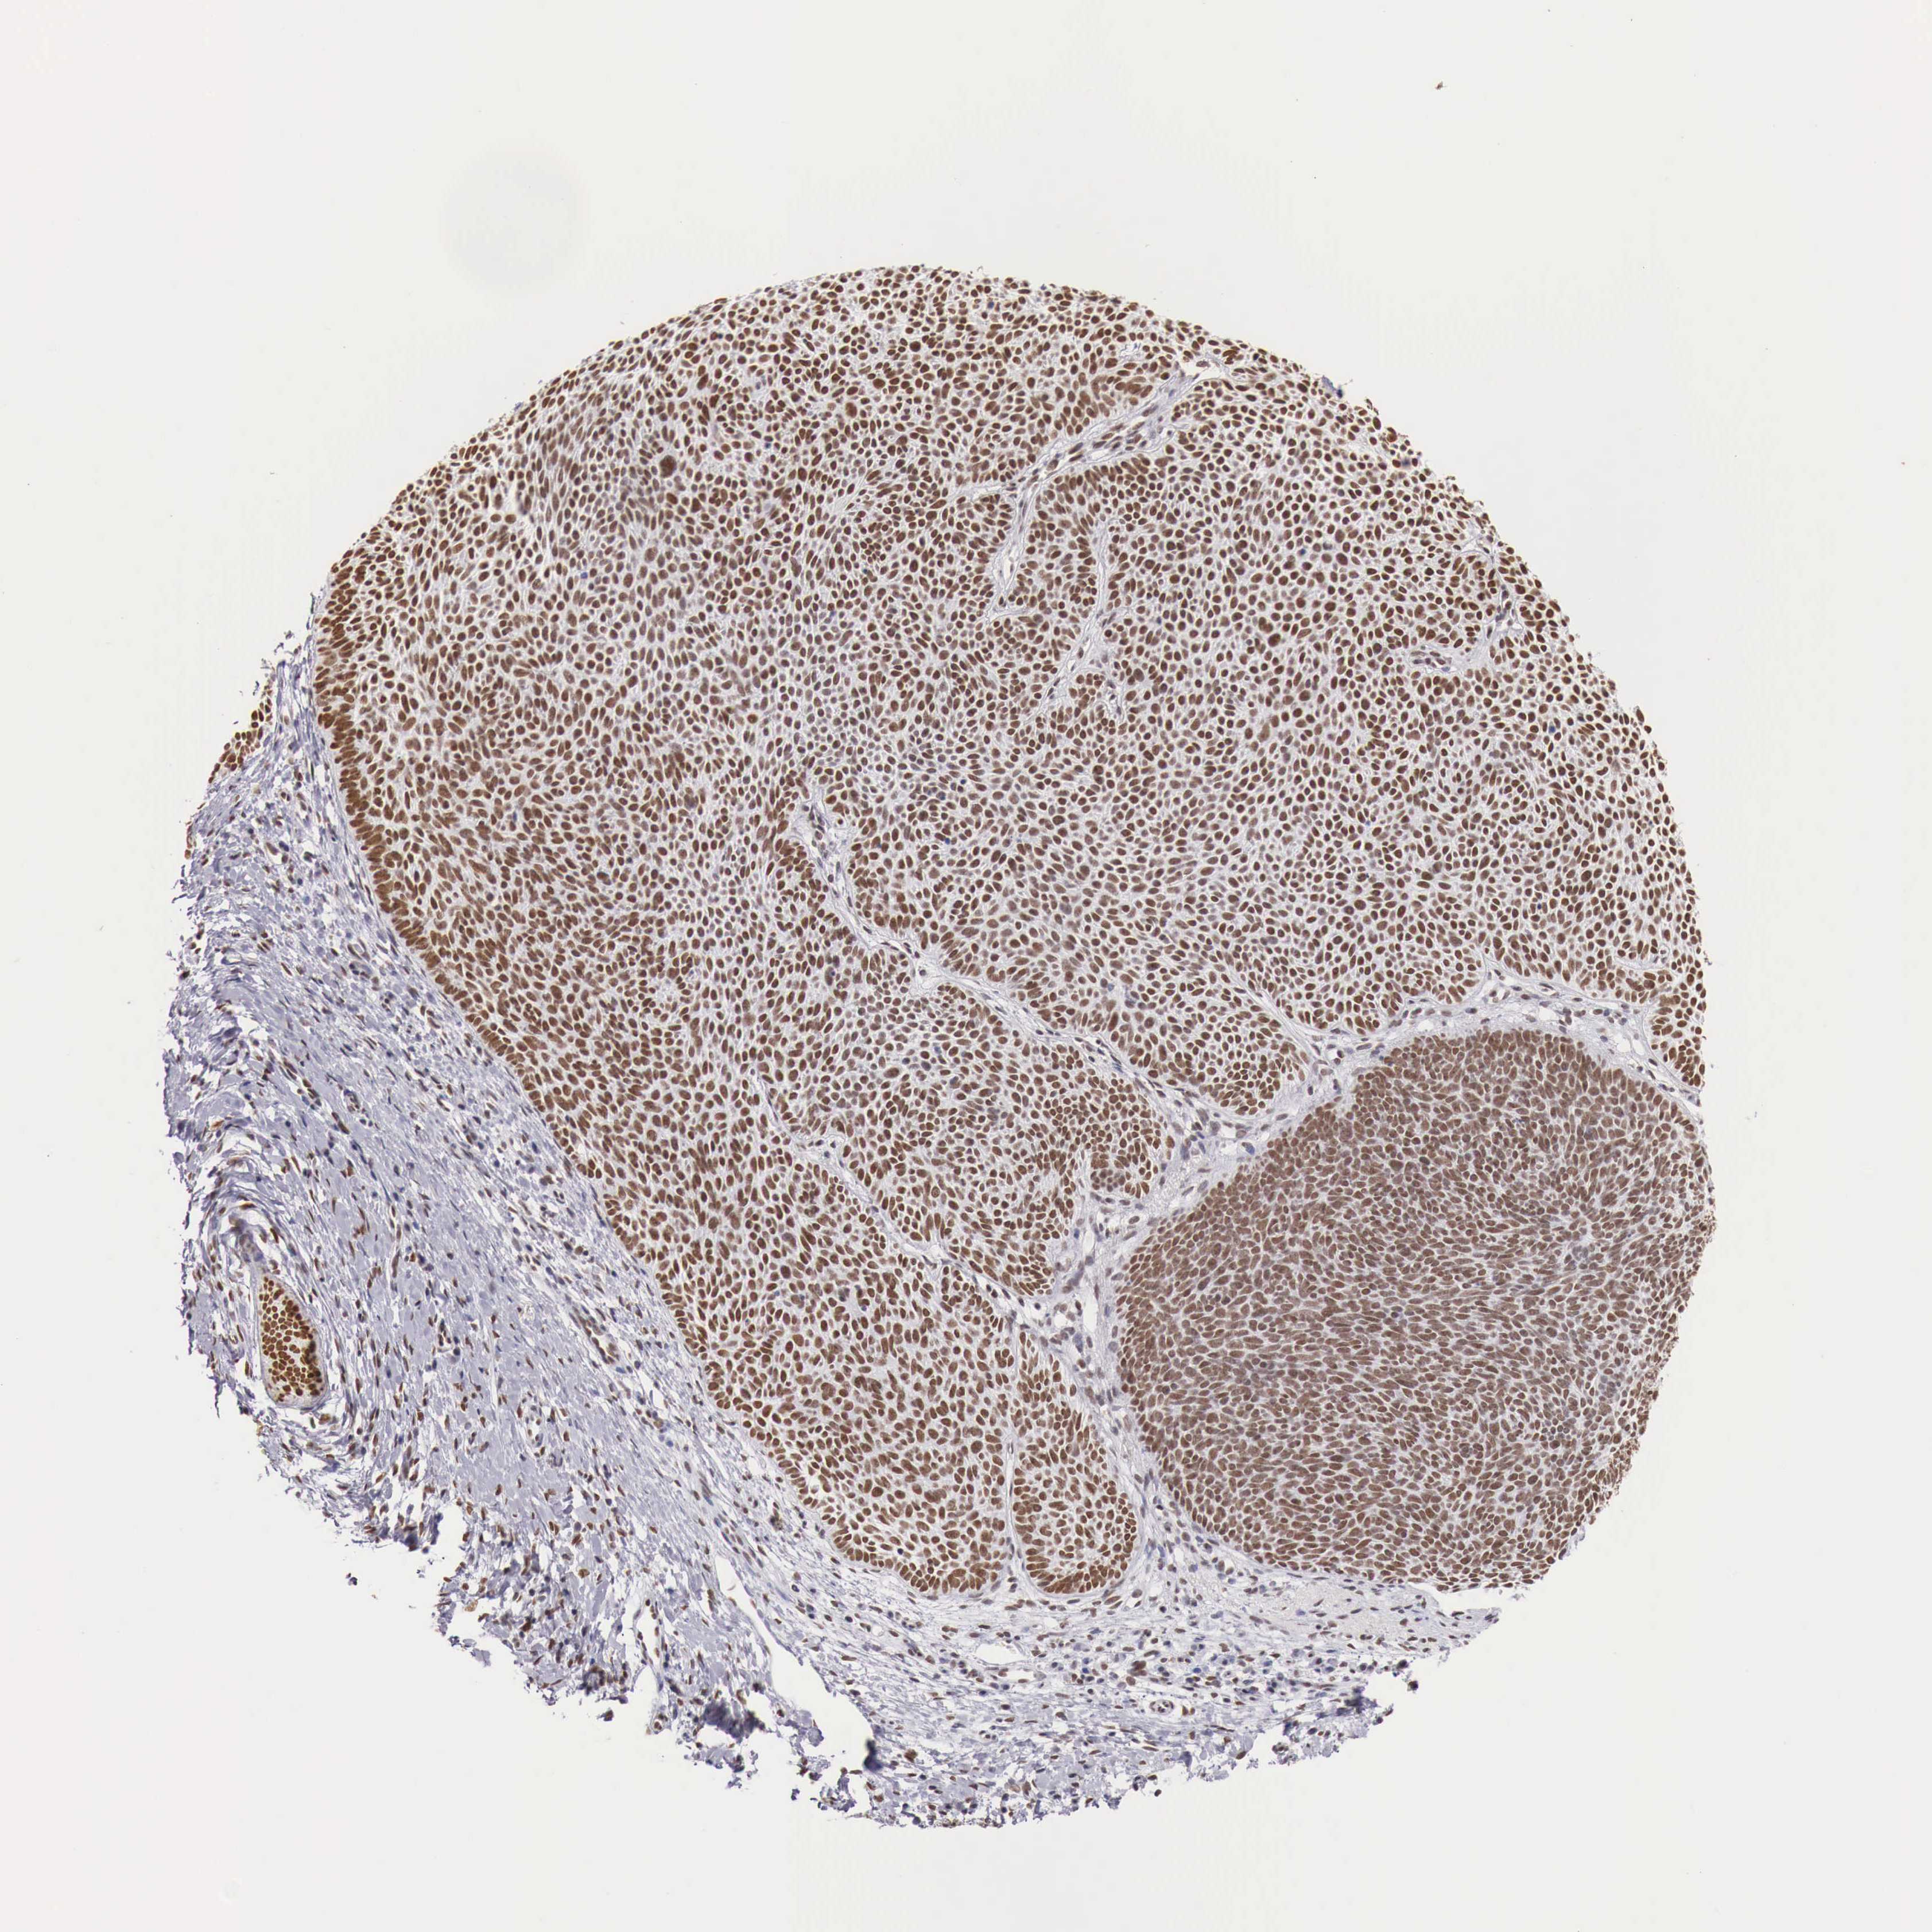

SKIN CANCER - Protein expressioni

A mouse-over function shows sample information and annotation data. Click on an image to view it in a full screen mode. Samples can be filtered based on level of antibody staining by selecting one or several of the following categories: high, medium, low and not detected. The assay and annotation is described here.

Each image is clickable and will lead to virtual microscopy that enables deeper exploration of all samples and also displays staining intensity scores, fraction scores and subcellular localization as well as patient and tissue information for each sample.

Antibody HPA000538

Staining

High

Intensity

Strong

Quantity

>75%

Location

Nuclear

Squamous cell carcinoma, NOS

Basal cell carcinoma